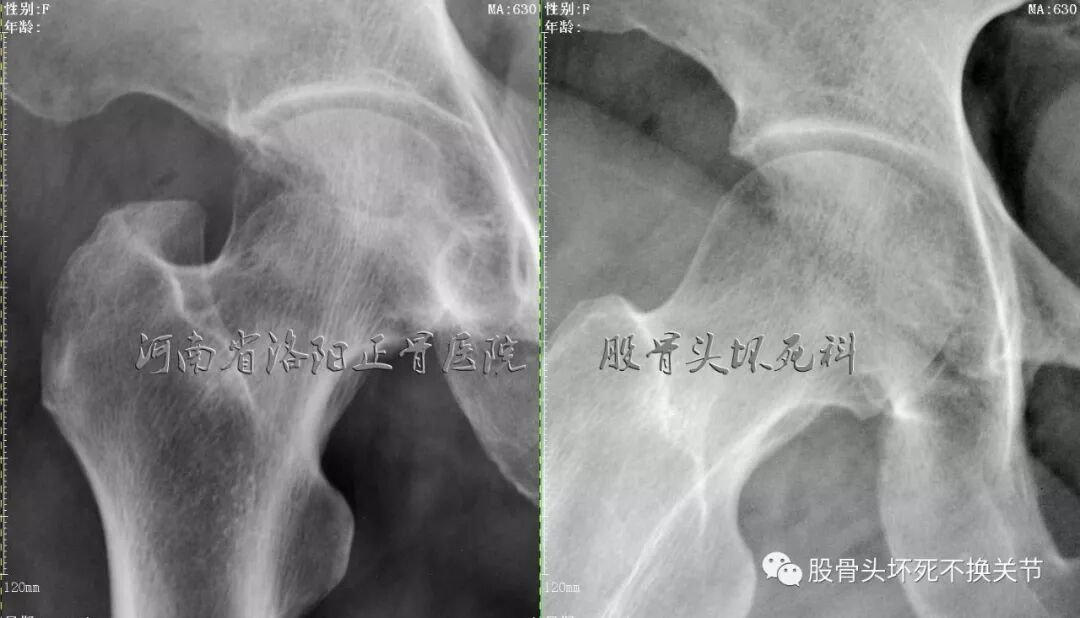

先看一下X光片:

骨盆蛙位片

右髋特写

从这些歪斜的X线片子可以看到,双髋关节并无特殊表现,双侧骶髂关节似乎轻微硬化(对于42岁生过孩子的女性来讲,不首先考虑病理原因);仔细研判放大了的右髋关节正位、蛙位片,可发现股骨头边缘轮廓并不是特别光整,与对侧相比右侧股骨近端整体骨密度低于对侧,对于一个长期患病、缺乏活动的关节来讲,不足为道,很常见。